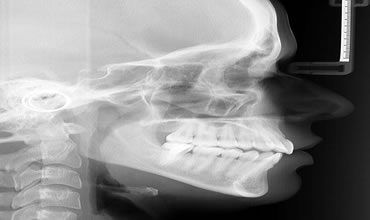

Telerradiografia

Serve para embasamento no tratamento ortodôntico pela análise cefalométrica. Documentar assimetrias craniofaciais.